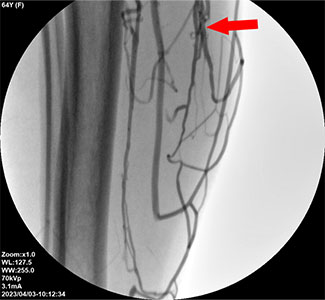

未能完全封闭问题静脉周围小静脉的逆流

此外,这也包括一些病例,即未检测到或漏诊了问题静脉周围小静脉的轻微逆流。

最终,未能完全封闭小静脉是复发的主要原因。